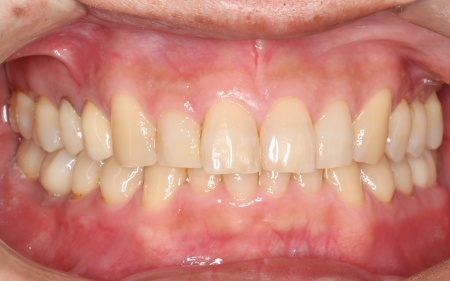

治療前